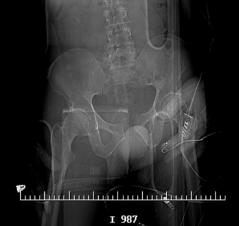

X-Rays and scans of the damaged right & left legs plus the pelvis

These x-rays were taken just after the accident. Some of the bones on the right leg have already been pushed back into the leg. The CT

scans show various views of the ankles and pelvis prior to any corrective surgery. Fibula bracing is clear in some of the images as well as

bracing that was used to secure the "open book" pelvis. In some of the last images it is apparent that the upper part of Liam’s left fibula is

broken. Liam was told that the pain he felt was most likely a muscle cramp. Nothing was done to repair this break and you will see in further

x-rays that the bone shifted and later fused in such a way as to add to the reduction of Liam’s leg length. The last photo shows the stint

used to block any potential blood clots from moving up.